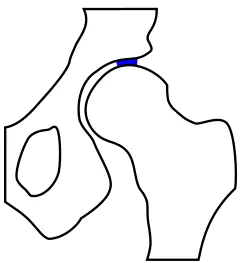

Klassische Ursache einer Arthrose stellt die Dysplasie von Gelenken dar. Am Beispiel der Hüfte wird deutlich, dass die mechanisch am meisten belastete Zone bei einer physiologischen Hüftstellung eine deutlich größere Fläche darstellt als bei einer dysplastischen Hüfte. Die Belastungen durch die auf das Gelenk einwirkenden Kräfte sind von der Gelenkform jedoch weitgehend unabhängig. Sie verteilen sich im Wesentlichen auf die Hauptbelastungszone(n). Dadurch wird bei einer kleineren Zone eine höhere Druckbelastung als bei einer größeren auftreten. Die biomechanische Druckbelastung des Gelenkknorpels ist somit bei einer dysplastischen Hüfte größer als bei physiologischer Hüftstellung. Diese Gesetzmäßigkeit wird allgemein ursächlich für das gehäufte Auftreten arthrotischer Veränderungen an von der anatomischen Idealform abweichenden tragenden Gelenken gesehen.